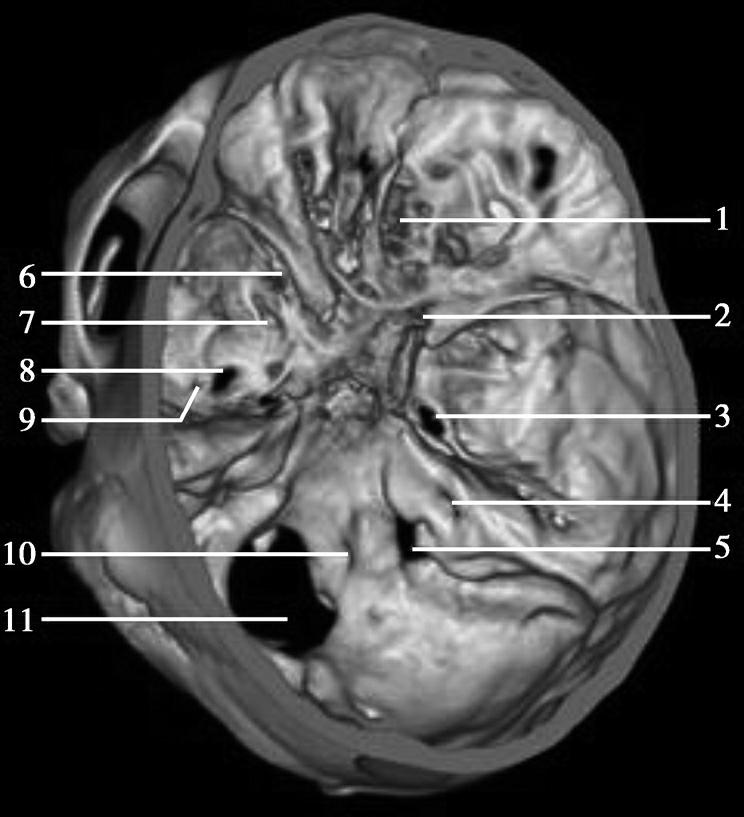

图1-2-2 颅底层面(骨窗)

A.横断面;B.横断面标注

1.鼻骨;2.筛窦纸板;3.颧骨眶突;4.翼腭窝;5.蝶骨大翼;6.卵圆孔;7.破裂孔;8.颞骨颧突;9.棘孔;10.斜坡;11.颞骨岩部;12.乳突;13.颈静脉孔;14.枕乳突缝;15.枕骨;16.枕内隆凸

层面前部呈开口向前的“V”字形,正中为鼻中隔,向两侧依次为筛窦和眼眶,眼眶内前部为眼球,后部为眶脂体。翼腭窝位于眼眶后部,窝内含有脂肪并有上颌神经通过。层面中部为蝶骨体,蝶骨体中部可见含气蝶窦,蝶窦后方为枕骨基底部,两者呈前后关系,其上面构成斜坡。蝶窦两侧为蝶骨大翼,其后外侧缘处由前向后可见卵圆孔和棘孔,分别有下颌神经和脑膜中动脉通过。斜坡外侧、岩骨尖前方为破裂孔。蝶骨大翼与眶外侧壁的颧骨借颧弓相连,颧弓和蝶骨大翼之间有咬肌及颞肌。层面中部外侧为外耳道。颞骨岩部呈“八”字形,相互之间借破裂孔软骨、蝶岩软骨结合和岩枕软骨结合连接。岩部后外侧的乳突部内可见乳突小房,乳突部与枕骨相接。岩骨后部可见颈静脉孔,内有颈内静脉、舌咽神经、迷走神经和副神经通过。层面后部为颅后窝,其内可见延髓,延髓前方为延髓前池,内有椎动脉,后外侧为小脑半球下部,后方为第四脑室、小脑扁桃体及小脑蚓部。

破裂孔、卵圆孔、棘孔及斜坡等均为重要的解剖结构,临床常见疾病如鼻咽癌常侵犯上述结构(图1-2-3)。颈静脉孔区较常见的肿瘤为颈静脉球瘤,常伴有颈静脉孔及其邻近骨质的破坏(图1-2-4)。